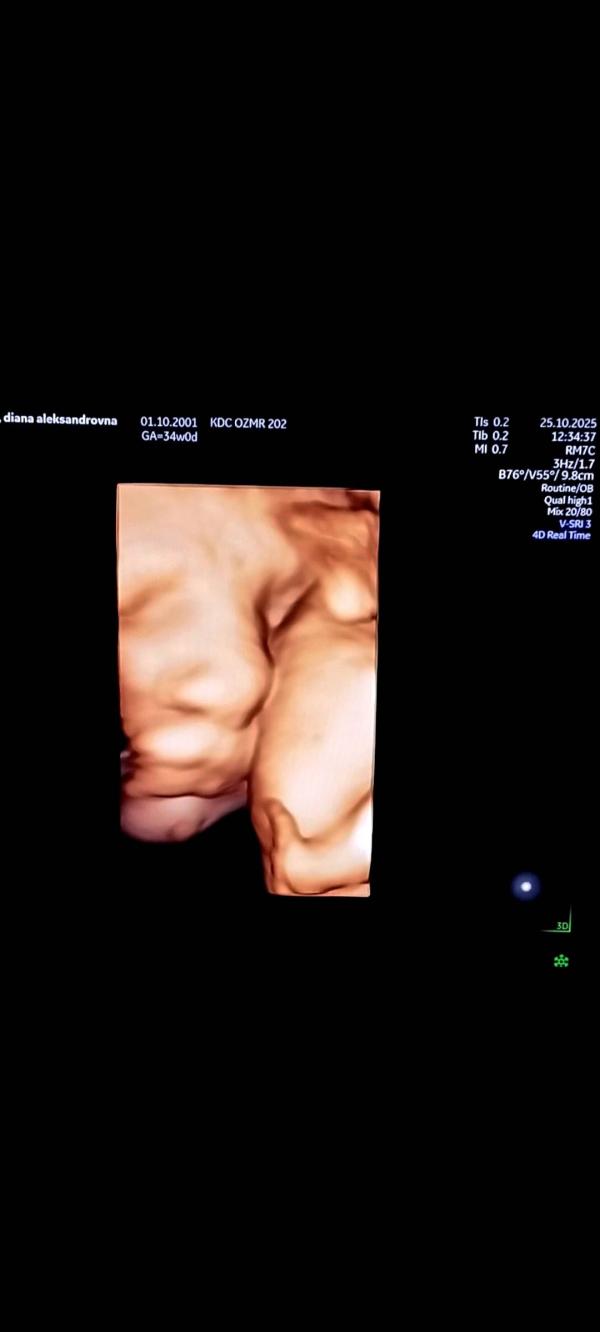

Третий скрининг успешно пройденный Региной Евгеньевной🩷

Срок 34.1 неделя, вес 2.471 грамм🩷🌹 Все замечательно, никаких отклонений, кровотоки сказали хорошие😍 Обвития нет, воды 15см, в головном (в тазовое сказали точно не перевернётся судя по картине) я счастлива 🥹🫶